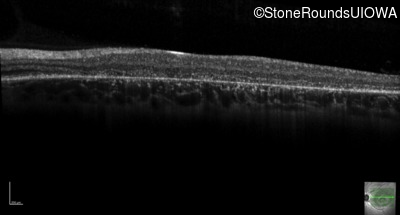

AR Stargardt Disease (IIA)

AR Stargardt Disease (IIA)

| Age at visit: 12 years |

| Age at visit: 13 years |

| Age at visit: 15 years |